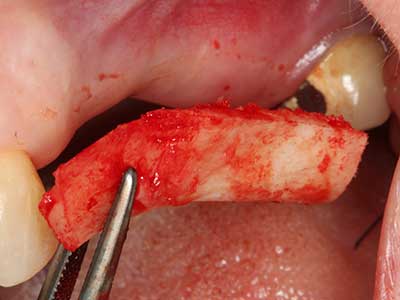

Пиезохирургията има допълнителни предимства при събиране на костни блокове. В допълнение към високата прецизност при остеотомията, описана по-горе, употребата на фините режещи накрайници значително намаляват загубата на материал. Голяма загуба на материал по време на събиране може да се очаква с дебелите накрайници, особено при употреба на борери Линдеман (Lakshmiganthan, Gokulanathan et al. 2012). Базалното разделяне, което е необходимо, особено за присадка на блок при ретромолар, е улеснено от специално създадени правоъгълни триони. В резултат на това, пиезохирургията е разглеждана като прецизна, улеснена и безопасна процедура за събиране на костни блокове в ретромоларното пространство (Happe 2007) (Фиг. 1-12).